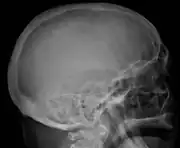

| Top: The most common site of bone lesions is the spine Bottom: Micrograph of a plasmacytoma, H&E stain | |

The diagnostic examination of a person with suspected multiple myeloma typically includes a skeletal survey. This is a series of X-rays of the skull, axial skeleton, and proximal long bones. Myeloma activity sometimes appears as "lytic lesions" (with local disappearance of normal bone due to resorption). And on the skull X-ray as "punched-out lesions" (pepper-pot skull). Lesions may also be sclerotic, which is seen as radiodense.[48] Overall, the radiodensity of myeloma is between −30 and 120 Hounsfield units (HU).[49] Magnetic resonance imaging is more sensitive than simple X-rays in the detection of lytic lesions, and may supersede a skeletal survey, especially when vertebral disease is suspected. Occasionally, a CT scan is performed to measure the size of soft-tissue plasmacytomas. Bone scans are typically not of any additional value in the workup of people with myeloma (no new bone formation; lytic lesions not well visualized on bone scan).

Skull X-ray showing multiple lucencies due to multiple myeloma -